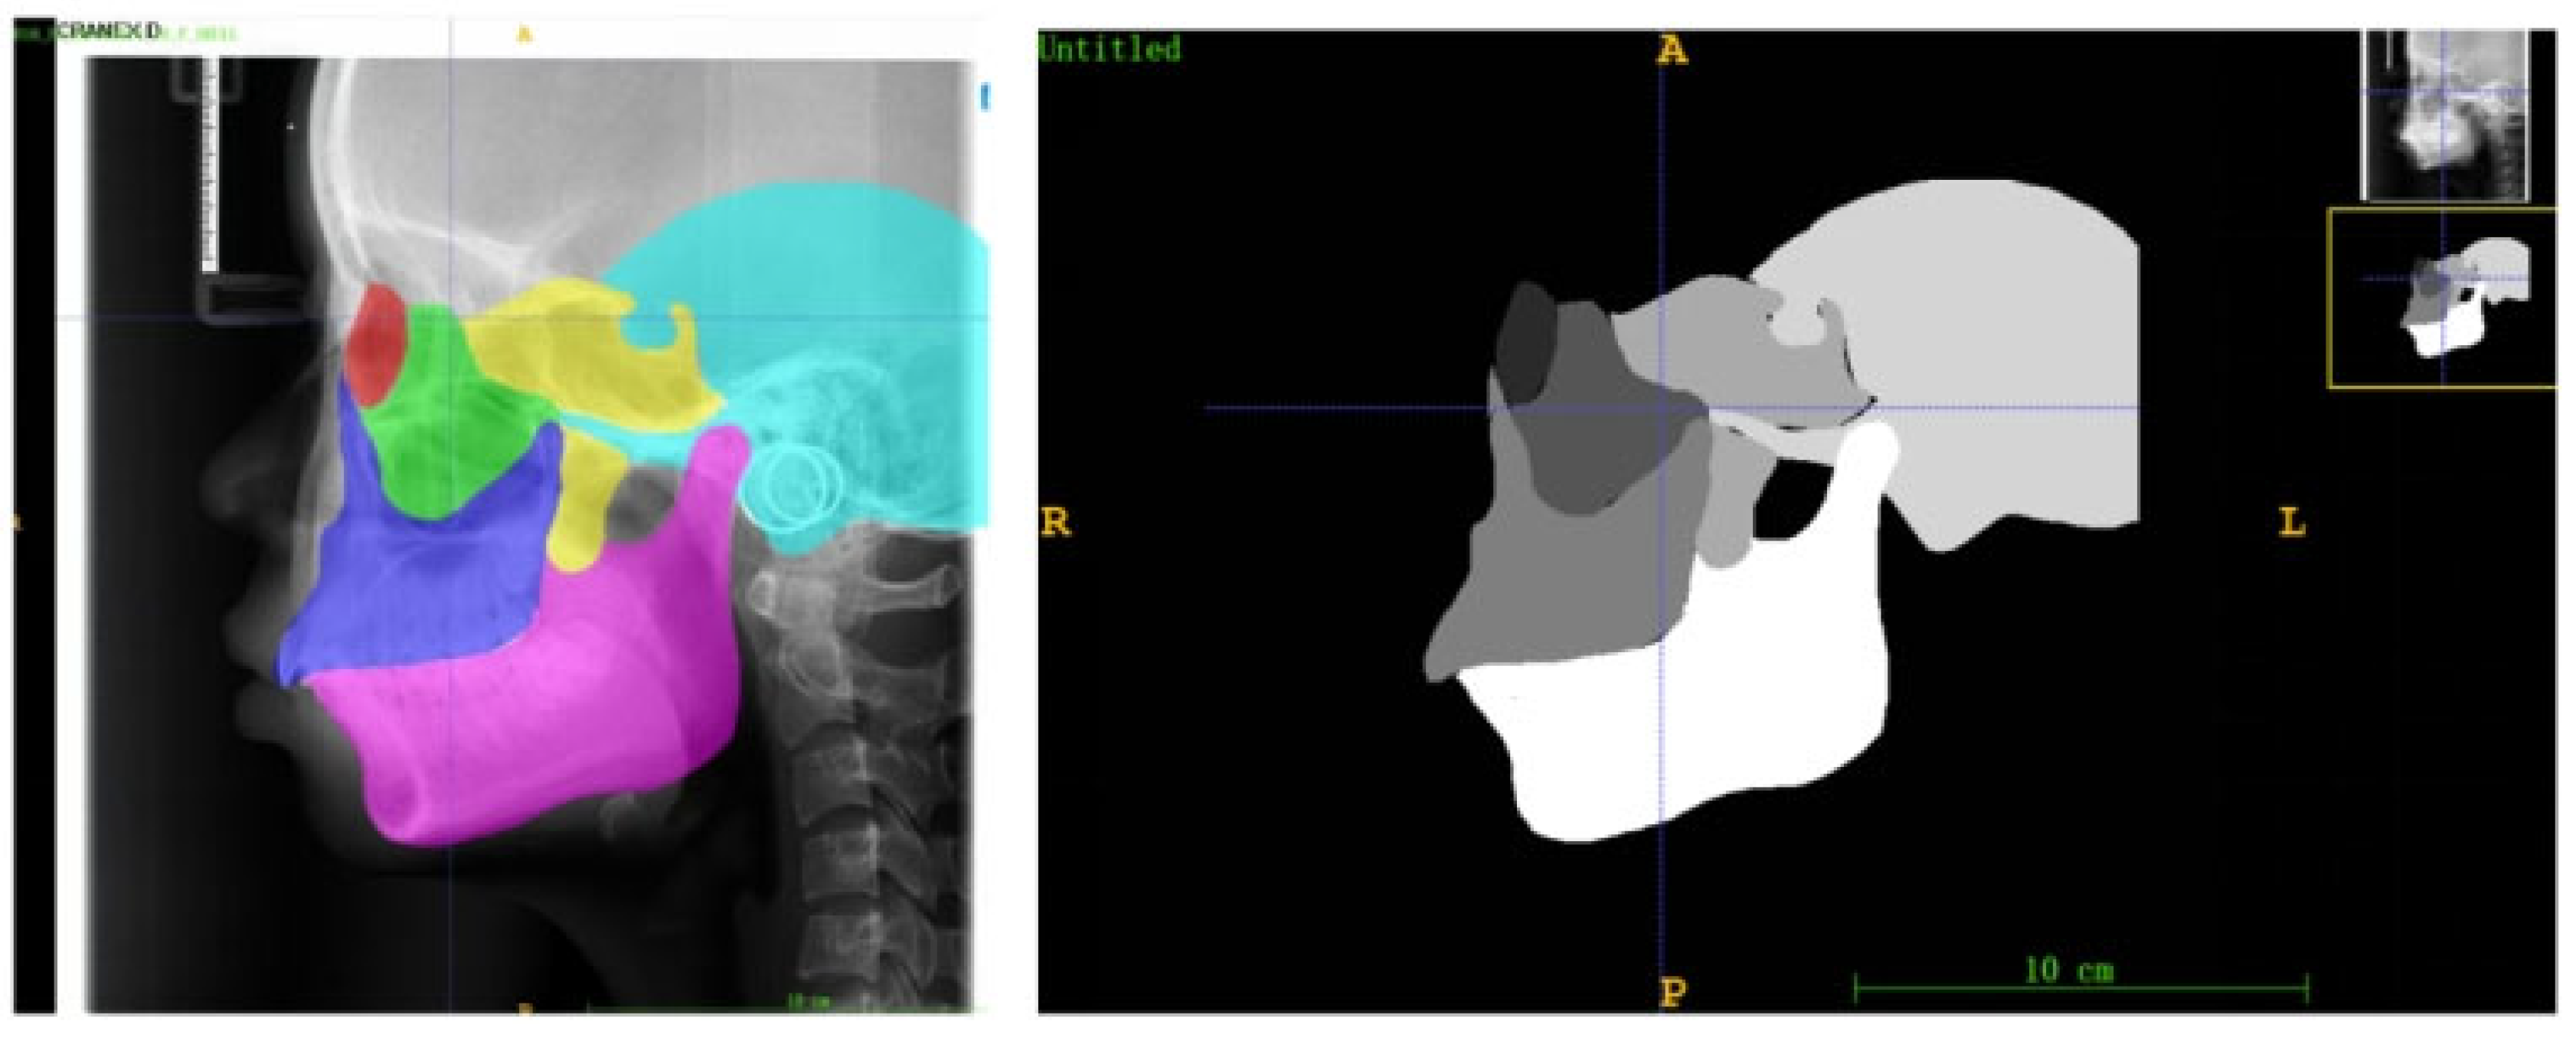

To quantitatively analyze the developmental saliency across the craniofacial complex, this study defined six core skeletal regions of interest (ROIs) on the lateral cephalometric radiographs (LCRs) based on their critical relevance in growth and development and their clinical significance: the orbital, zygomatic, maxillary, pterygoid, temporal, and mandibular regions (Figure 5). These regions were selected because they collectively cover the skeletal structures that undergo significant changes during craniofacial growth and development, and are representative of understanding growth chronology, spatial coordination, and the expression of sexual dimorphism.

Figure 5.

Examples of anatomical zone templates for an 18-year-old male, which contain delineations of the six craniofacial skeletal regions (red: socket; green: zygoma; blue: maxillae; yellow: sphenoid bone; blue: temporal bone; pink: mandible).

The selection and delineation of these regions were based on their identifiable boundaries formed by established cephalometric landmarks and characteristic radiographic anatomy:

Orbital region: The quadrilateral radiolucent area bounded by the superior and inferior orbital rims and the lateral orbital margin.

Zygomatic region: The dense, anteriorly convex radiopacity corresponding to the zygomatic body, anteriorly connected to the zygomaticofrontal and zygomaticomaxillary sutures, and posteriorly to the zygomatic arch.

Maxillary region: The quadrilateral radiopaque area comprising the maxillary body, extending from the infraorbital rim superiorly to the alveolar process inferiorly, with the posterior boundary at the pterygomaxillary fissure, and containing the maxillary sinus radiolucency.

Sphenoid region: Includes the sella turcica, dorsum sellae, and clinoid processes; the pterygoid plates located posterior-superior to the maxillary tuberosity; and the pneumatized sphenoid sinus.

Temporal region: Primarily the squamous part, forming the curved bony plate of the lateral wall of the middle cranial fossa, bounded superiorly by the temporal line and with the glenoid fossa anteroinferiorly.

Mandibular region: The continuous, horseshoe-shaped radiopacity encompasses the mandibular body, ramus, condyle (within the glenoid fossa), and coronoid process.

To ensure comparability of quantitative analyses across all subjects, age- and sex-specific anatomical templates were constructed for each ROI. First, 20 LCR images were randomly selected for each year of age and for each sex from the overall dataset. An experienced orthodontist manually segmented the six ROIs on every image in this subset using ITK-SNAP software (Insight Toolkit - Snake Automatic Partitioning, Version 3.8; University of Pennsylvania, USA). The segmentation results from these 20 LCRs for each age-sex group were then averaged to generate a consensus mask for each ROI (Figure 5).